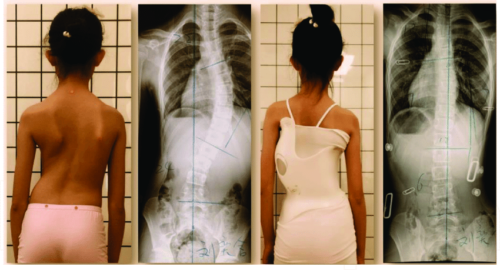

يُعد اعوجاج العمود الفقري (الجنف) من الحالات الشائعة التي تصيب الأطفال والمراهقين خلال مراحل النمو، ويمكن أن تستمر أو تظهر في مرحلة البلوغ. ومن بين العلاجات غير الجراحية الفعالة التي تُستخدم لتقويم العمود الفقري وتقليل تطور الانحناء، يبرز الحزام الطبي أو الجبيرة القطنية كأحد الحلول الأساسية، لكن يبقى السؤال: متى يجب البدء في استخدام الحزام؟ ومتى يكون غير فعال؟

توصي الجمعية الدولية للجنف باستخدام الحزام الطبي في الحالات التالية:

انحناء يتراوح بين 25° و45° لدى المرضى الذين لا يزالون في مرحلة النمو.

انحناء أقل من 25° لكنه يتطور بمعدل يزيد عن 5° خلال ستة أشهر.

حالات الجنف بين 20° و25° عند وجود علامات واضحة لعدم اكتمال النضج الهيكلي (مثل Risser 0 أو Tanner 1-2).

وفي هذه المراحل، يُعتبر الحزام خيارًا فعالًا للحفاظ على استقامة العمود الفقري وتفادي تدهور الحالة.

استخدم الحزام في حالات الانحناء من 25° إلى 40°، خاصة في مراحل النمو المبكر.

تأكد من عدم وجود تحدب صدري حقيقي أو حالات متقدمة فوق 45°.